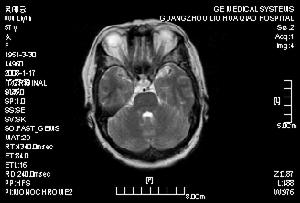

6.磁共振(MRI) MRI 對腔隙性腦梗死的檢出率明顯優於頭顱CT 掃描,尤其對腦幹及小腦內的腔梗病灶。病後72h,75%患者的MRI 可顯示≤15mm 的腔隙性病灶,5 天內其檢出陽性率可達92%。急性期腔梗病灶在MRI 的影像特點為T1信號減低、T2 信號增高,其中以T2 信號增高改變更為敏感。